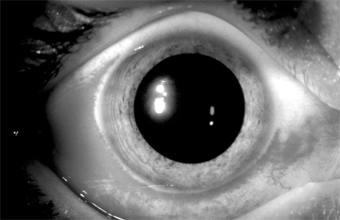

In adults, the conjunctiva of both tarsi-especially the lower tarsus-have papillae and follicles (Figure 5-3). Since pseudomembranes do not usually form in the adult, scarring does not usually occur. Superficial keratitis may be noted superiorly and, less often, a small superior micropannus (< 1-2 mm). Subepithelial opacities, usually marginal, often develop. Otitis media may occur as a result of infection of the auditory tube.

Figure 5-3: Acute follicular conjunctivitis caused by inclusion conjunctivitis in a 22-year-old man with urethritis. (Courtesy of K Tabbara.)